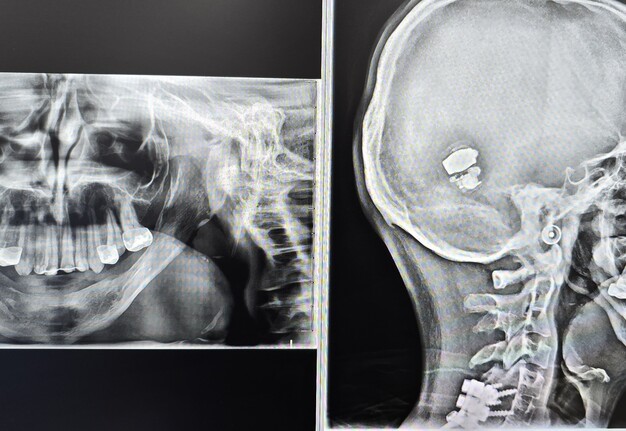

He originally underwent bilateral mandibular DO at the age of two years for airway obstruction. Persistent mandibular hypoplasia into adulthood required a repeat DO at age 19, achieving approximately 18-23 mm advancement at 1 mm/day. As reported in syndromic craniofacial literature, long-term mandibular form after distraction can remain suboptimal due to altered growth vectors and limited intrinsic regenerative capacity [6-8, 15]. Postoperative imaging demonstrated inadequate mandibular width and incomplete consolidation (Fig 1).

Following his second DO and due to persistent a thin mandibular alveolar ridge, bone morphogenetic protein (BMP)-augmented allograft reconstruction was attempted about half a year later but failed to generate sufficient bone volume. This finding is consistent with reports of variable graft success in congenital mandibular deficiency [16]. Given two prior distraction attempts, graft failure, and the morbidity associated with fibula free-flap mandibular reconstruction, a CAD-CAM titanium subperiosteal implant was selected as definitive treatment. Patient has agreed to the proposed treatment and has signed consent form also for documentation and publication of his case.